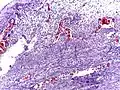

Pathology

Even for clinically certain appendicitis, routine histopathology examination of appendectomy specimens is of value for identifying unsuspected pathologies requiring further postoperative management.[69] Notably, appendix cancer is found incidentally in about 1% of appendectomy specimens.[70]

Pathology diagnosis of appendicitis can be made by detecting a neutrophilic infiltrate of the muscularis propria.

Periappendicitis (inflammation of tissues around the appendix) is often found in conjunction with other abdominal pathology.[71]

Micrograph of appendicitis and periappendicitis. H&E stain

Micrograph of appendicitis showing neutrophils in the muscularis propria. H&E stain

Acute suppurative appendicitis with perforation (at right). H&E stain